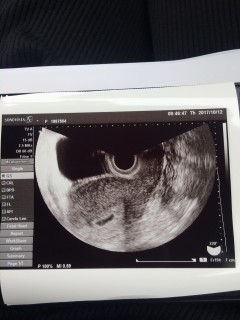

初診のエコー写真です。 この頃はまだ双子だということが判明していませんでしたが、次の検診の9w4dに先生から「2つあるから双子だね」と言われてびっくりしました。